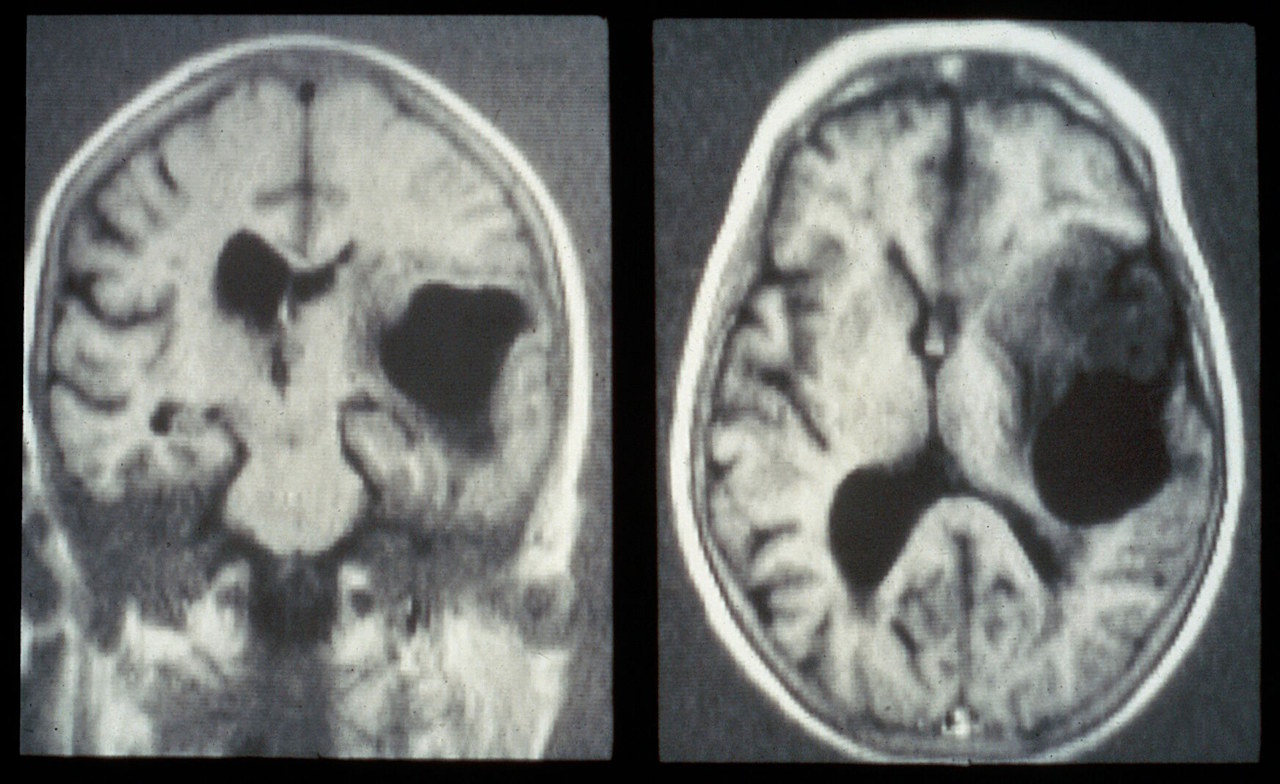

Пухлини гліобластоми в мозку мишей і накопичення ліків з наночастинками всередині них (фото справа, темніший коричневий позначає найбільше накопичення ліків у пухлині). Mahajan et al. / PNAS, 2025